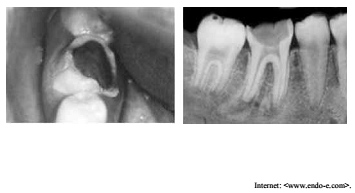

As imagens precedentes referem-se a um paciente com

quatorze anos de idade que procurou atendimento odontológico,

queixando-se da presença de uma gengiva no meio de um dente do

lado direito.

Considerando as imagens apresentadas, assinale a opção correta.